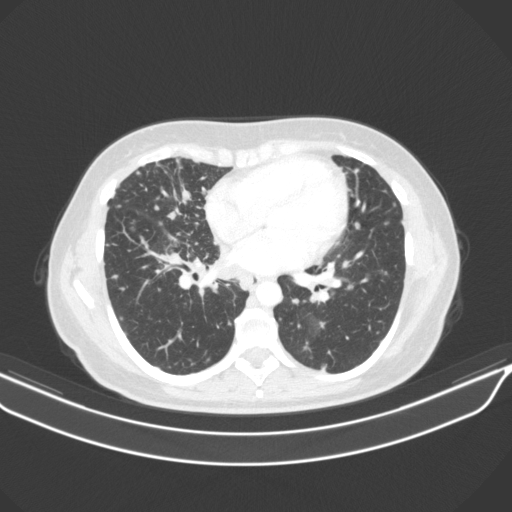

Slice 70 Targeting Evaluation

Slice: Slice_70

Conversion: NATIVE β†’ VENOUS

Targeted Slice 70 - Lung Window Analysis (Generated vs Real Venous)

0.728

Lung SSIM

109.0

Lung RMSE

48.5

Lung MAE

Average Lung Window Metrics Across All Slices (133 slices) - Generated vs Real Venous

0.727

Lung SSIM (Avg)

108.6

Lung RMSE (Avg)

46.1

Lung MAE (Avg)